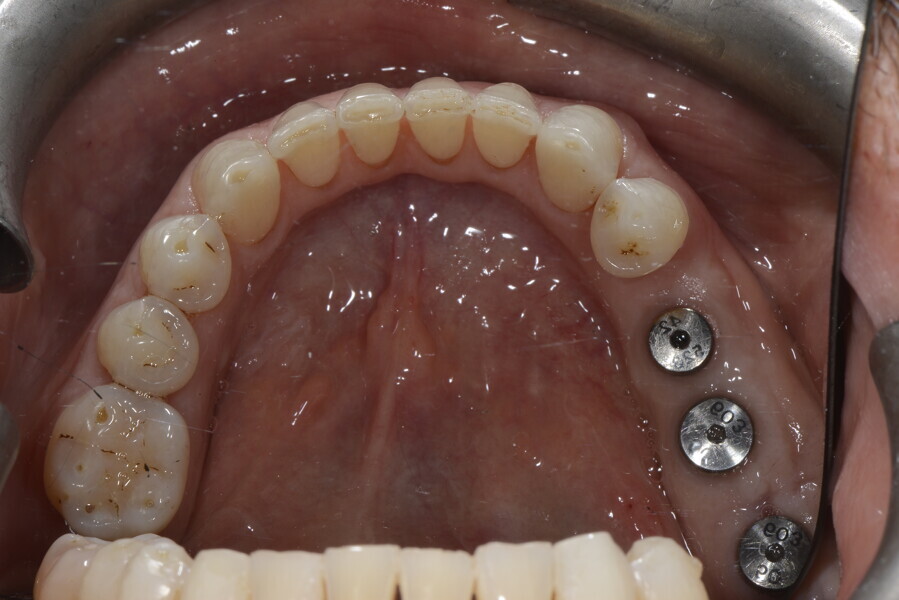

5. sinus lift for bone regeneration and implant placement with periodontal surgery where needed; and

6. ceramic veneers in the anterior area and crowns on the implants in the posterior area.

This patient, like all patients requiring interdisciplinary rehabilitation, had to first undergo periodontal treatment and caries restoration (Fig. 17). At the same time, it was important to rehabilitate swallowing with Froggymouth and relax the masticatory muscles and relieve the TMJs with an occlusal device. We could then study the orthodontic treatment plan using Invisalign ClinCheck (Align Technology) and showed the treatment plan to the interdisciplinary team and to the patient (Fig. 18). We were then able to create the correct sequence of orthodontic treatment, bone augmentation and implant surgery needed for the posterior edentulous spaces.

After the first phase of aligner treatment, we had achieved better inter-arch coherence, better maxillary arch expansion, and some space for improving the anterior tooth proportions restoratively (Fig. 19). We then temporarily restored the anterior teeth directly with composite, closing the spaces, improving the tooth proportions and further increasing the maxillary arch expansion (Fig. 20). We used restorative arch expansion to reduce the orthodontic destabilisation of the teeth to achieve the correct inter-arch coherence and retain the teeth in the cortical bone.38 A refinement aligner phase was undertaken to improve the final alignment of the gingival zenith and to improve the inter-arch coherence (Fig. 21). The periods of the first orthodontic phase and of the refinement were used to augment the mandibular and maxillary bone and to place the implants (Fig. 22). At the end of the orthodontic treatment, the case was finalised with ceramic veneers in the anterior area and temporary restorations on the implants in the posterior area (Figs. 23–26).

The provisional phase of about four months was important to allow the peri-implant tissue to mature and to teach the patient to chew correctly with chewing gum, cotton rolls and silicone masticatory sticks. This is fundamental training for the patient to achieve the correct alternating unilateral masticatory cycle needed to obtain the ideal rehabilitation of the masticatory system. We wanted the patient to achieve ideal masticatory and swallowing function. After sufficient rehabilitation time, we finalised the case with posterior zirconia crowns screwed on to the implants (Fig. 27).26